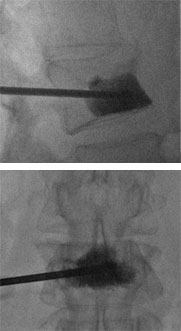

Введение костного цемента в тело позвонка производится через специальную иглу, контроль над манипуляциями осуществляется при помощи рентгенографии. В последнее время хирургические методики, построенные на использовании костного цемента (ПММА – полиметилметакрилата), находят всё более широкое применение при различного рода патологиях, затрагивающих позвоночный столб.

Суть методики заключается в том, что хирург вводит в тело повреждённого позвонка металлическую иглу, через которую (под компьютерно-томографическим и флюороскопическим контролем) вводится специальная смесь. Смесь состоит из костного цемента, основанного на ПММА, контрастирующего материала и антибиотика. Введение в тело позвонка указанной иглы при патологиях поясничного и грудного уровня производится транспедикулярно, тогда как при патологиях шейного уровня применяется передний боковой доступ.